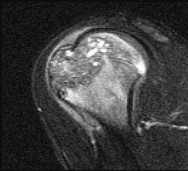

Question 67

A 65-year-old male presents with new-onset groin pain and a palpable mass 6 years following a primary Metal-on-Polyethylene (MoP) total hip arthroplasty (THA).

A MARS MRI demonstrates a solid and cystic soft-tissue mass. Laboratory testing reveals elevated serum Cobalt levels (>10 ppb) with relatively normal Chromium levels. Infection is ruled out. What is the most likely underlying mechanism for his presentation?

Explanation

The clinical scenario describes trunnionosis, or mechanically assisted crevice corrosion (MACC), occurring at the modular head-neck junction (trunnion) of the femoral stem. In a Metal-on-Polyethylene (MoP) THA, elevated cobalt levels in the presence of normal chromium levels strongly suggest corrosion at a modular junction (typically a CoCr head on a titanium stem), not bearing surface wear. This process can lead to an adverse local tissue reaction (ALTR/ALVAL) and pseudotumor formation.